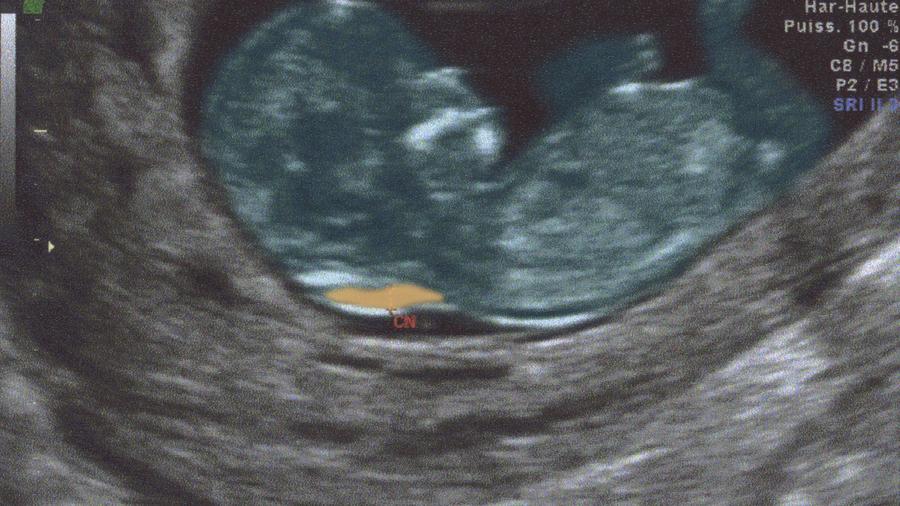

Zunächst führen wir bei ihrem Kind eine umfangreiche Ultraschalluntersuchung durch. Beim Ersttrimester Screening können zu einem sehr frühen Untersuchungszeitpunkt Fehlbildungen ausgeschlossen werden. Die bekannteste Untersuchung des Ersttrimestertests ist die Nackenfaltenmessung.

Das Ersttrimesterscreening wird im ersten Schwangerschaftsdrittel zwischen der 11. Das Ersttrimesterscreening wird im ersten Schwangerschaftsdrittel zwischen der 11. Dabei untersuchen Ärzte das Kind auf mögliche Chromosomenbesonderheiten.

Und der 14Schwangerschaftswoche durchgeführtHierfür wird neben der Untersuchung des mütterlichen Blutes auf bestimmte Schwangerschaftswerte eine hochauflösende Ultraschalluntersuchung des Ungeborenen gemacht. Zusätzlich kann eine Risikoberechnung für Chromosomenstörungen des Kindes durchgeführt werden. Und der 14Schwangerschaftswoche durchgeführtHierfür wird neben der Untersuchung des mütterlichen Blutes auf bestimmte Schwangerschaftswerte eine hochauflösende Ultraschalluntersuchung des Ungeborenen gemacht.